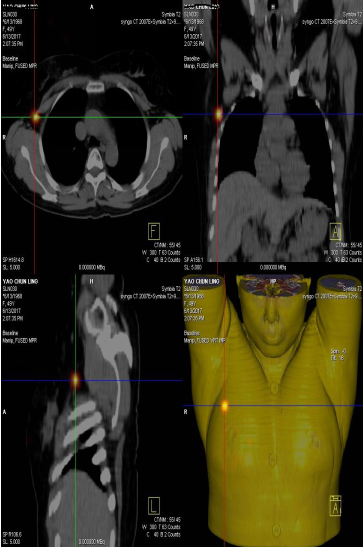

前哨淋巴結(jié)顯像技術(shù)一般在腫瘤附近注射放射性核素標(biāo)記特殊藥物,這種藥物會(huì)被前哨淋巴結(jié)攝取,存在于前哨淋巴結(jié)中。24小時(shí)之內(nèi)都可用SPECT-CT進(jìn)行前哨淋巴結(jié)顯像檢查。

找到幾個(gè)淋巴結(jié)沒有明確的限制,淋巴結(jié)核素計(jì)數(shù)小于第一個(gè)SLN計(jì)數(shù)的10%就不再是前哨淋巴結(jié)了。

患者李女士,發(fā)現(xiàn)右側(cè)乳腺腫物,來我院就診,行乳腺腫物局部擴(kuò)大切除術(shù),術(shù)后病理回報(bào):右乳腺浸潤(rùn)性導(dǎo)管癌III級(jí),伴原位癌。擬行右乳腺癌切除術(shù),提檢前哨淋巴結(jié)顯像檢查,明確有無淋巴結(jié)轉(zhuǎn)移。